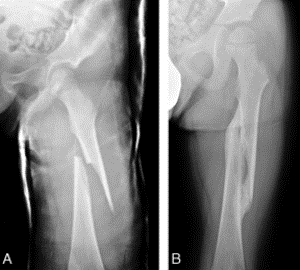

Смещение отломанных мелких частиц отличается разнообразием: в боковом направлении, в длину, под наклоном и ротационное, которые зависят от месторасположения травмы в диафизе. Таким образом, при правмировании в верхней 1/3 центральная отломанная частица отклоняется вперед и кнаружи. Отдаленный отломок под воздействием мышцы- супинатора — внутрь и кзади. Все эти механизмы вызывает клиническое деформирование по типу галифе.

Нарушение целостности в средней диафизарной части не вызывает какого-то особо смещения, но иногда значительно отломки отклоняются вертикально.

Повреждение в нижней части вызывает следующее отклонение: центральный отломок под воздействием мышцы-супинатора отклоняется внутрь, а периферический — под воздействием мышцы-пронатора (икроножной) в заднем направлении.

Обязательно осмотр пациента завершается рентгенографическим исследованием с целью уточнения характера повреждения и диспозиции отломков.